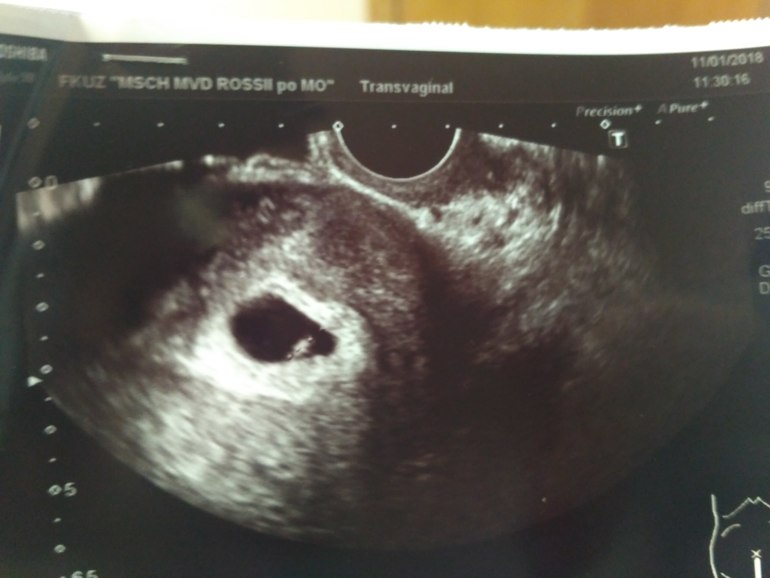

УЗИ- 05.01 - ПЯ 5мм и все(это 5 недель ровно); сегодня ПЯ-15мм, КТР-5 мм, СБ+

Опять сердце не на месте, что не так с этим желточным мешочком? Кто сталкивался с таким? На снимке вроде только эмбрион...